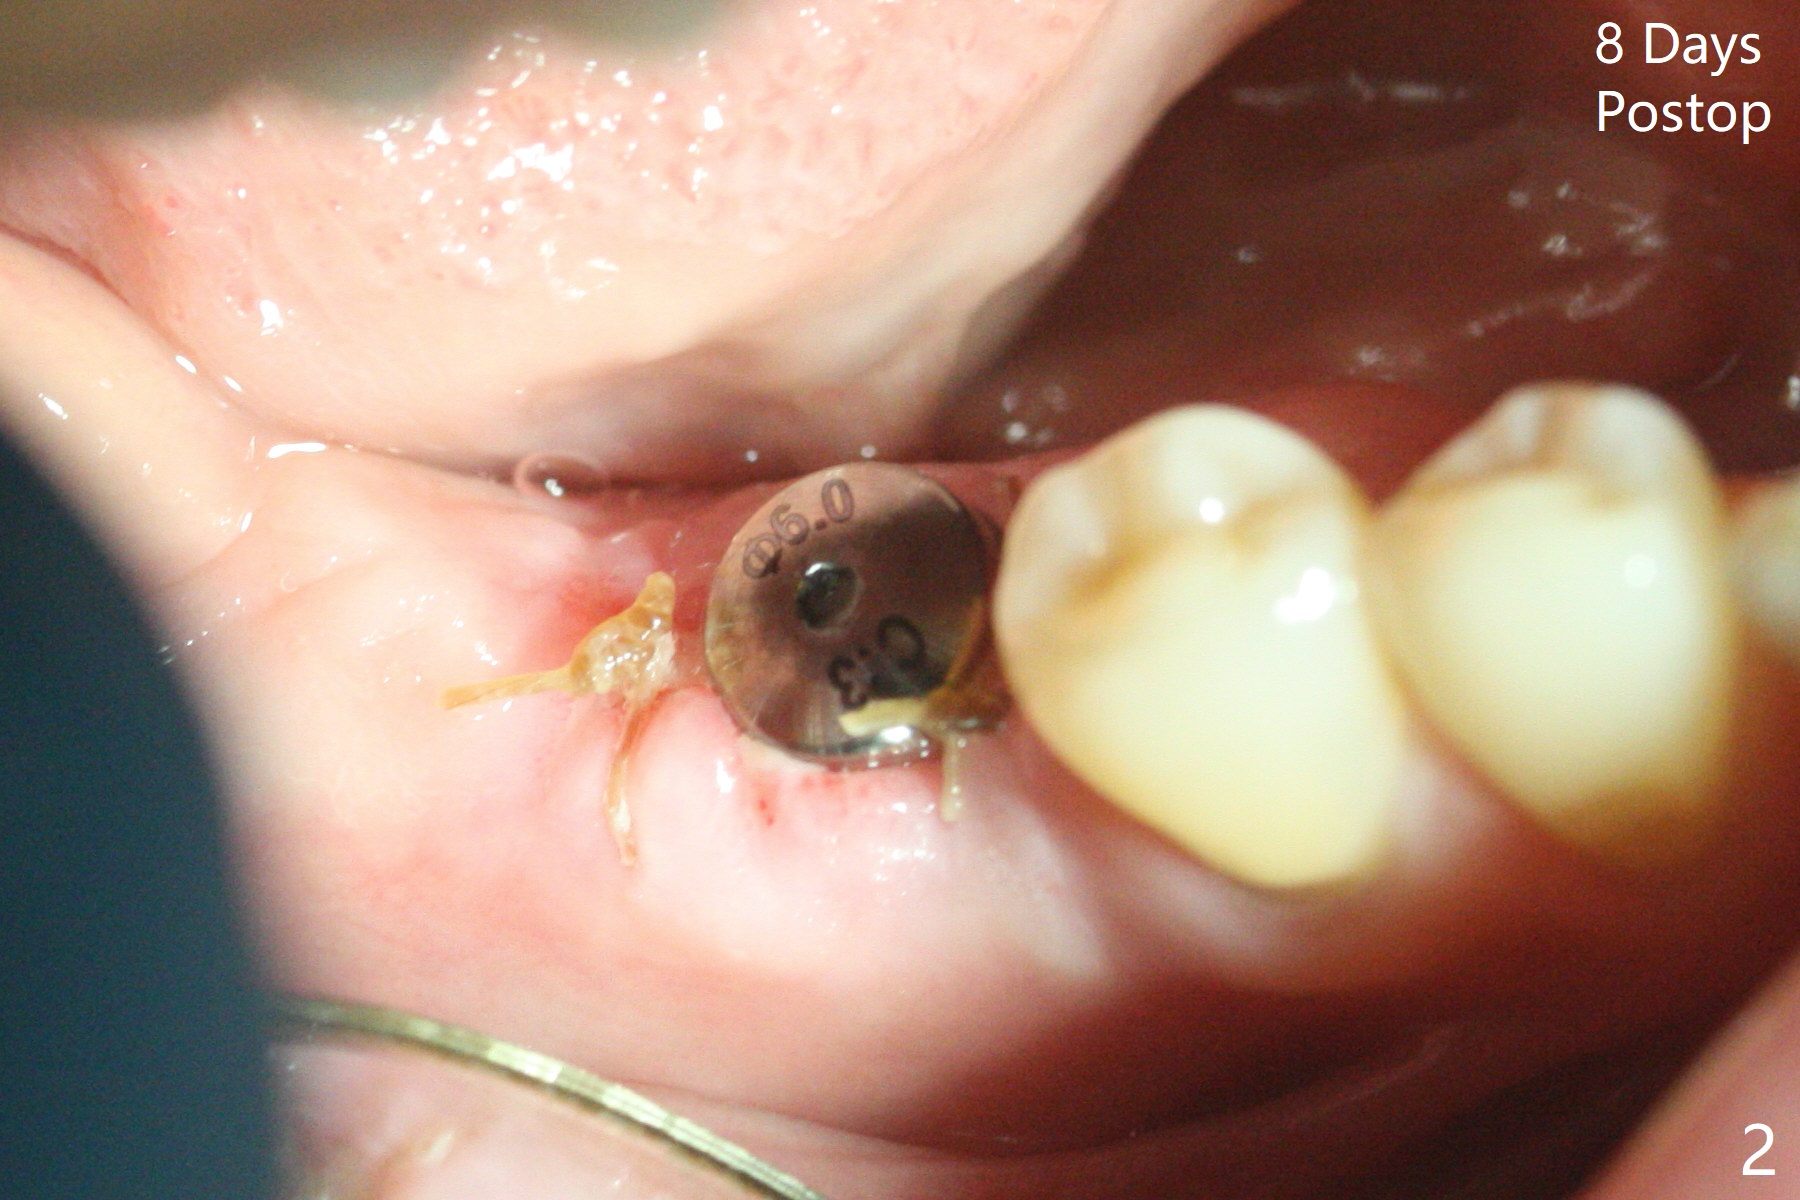

右下7(以前近中倾斜移位)位点保留后13月回来做6导板种植,骨质密度高,钻洞慢,注意灌溉制冷,使用4.5毫米功螺纹钻头后,植入4.5x9毫米植体(图一:牙槽嵴下~1毫米,扭力大约35Ncm)。使用5.5和6.0毫米profile drills后,放置6x3毫米愈合基台,最后植体,基台周围放置自体骨(事先翻瓣)。看样子邻牙植骨(图一:白线)对植牙有帮助。翻瓣缺点是缝合后伤口保护,牙周敷料术后一两天脱落(远中植体最好使用修复基台,不容易脱落),造成病人恐慌,第二次敷料术后第七天脱落,可欣的是伤口术后第八天愈合(图二)。术后四个月更换基台(图三),调整高度后,取模。由于基台边缘龈上,先拧紧(30 Ncm)后粘固,之后不再取出基台。然后对合取模,修改对合牙冠。